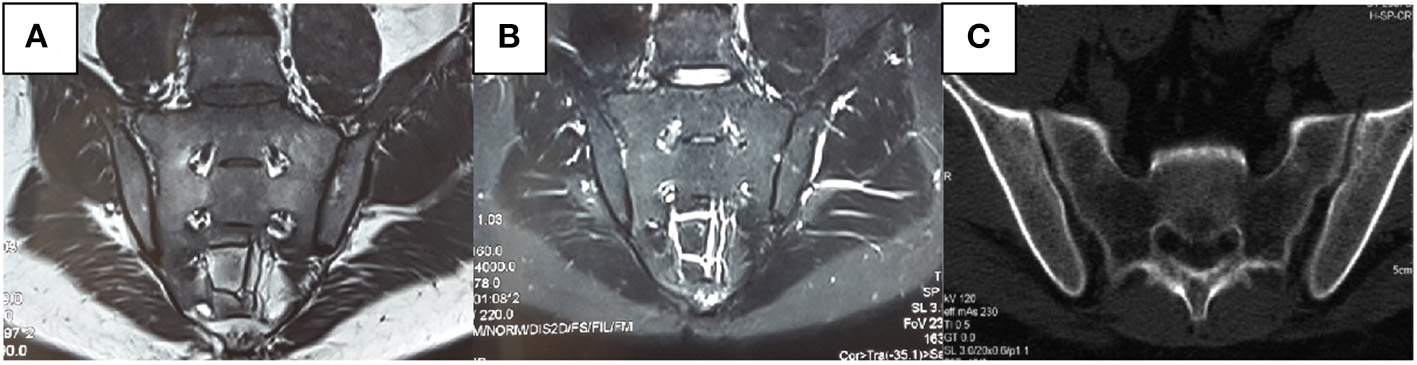

We also found that radiological abnormalities were another main cause of misdiagnosis, in addition to clinical symptoms. Five patients in our study had been misdiagnosed with SpA/AS due to SIJ–computed-tomography (CT)/X-ray abnormalities. Abnormalities in conventional radiology mainly present as coarse SIJ with a lack of smooth bone (Figure 3). Ten patients had been misdiagnosed due to SIJ–MRI abnormalities, seven of whom met the definition for positive SIJ–MRI for patients with SpA (6). In 2019, the ASAS–MRI working group redefined SIJ–MRI abnormalities (7). The group believed that even though SIJ–MRI presentation might suggest SpA, there is a need to combine clinical presentation, laboratory tests, and other markers. Therefore, osteoarthritis, infection, trauma, tumors, and artifacts in osteomalacia can mimic MRI presentations of patients with SpA. In our current study, we found that patients with osteomalacia could develop BME, but the OR of this finding was 0.995 (CI: 0.939–1.088). Therefore, BME on MRI has little risk for osteomalacia. However, bone erosion score in osteomalacia was significantly lower than in SpA/AS; its OR was 0.551 (CI: 0.325–0.934), and the area under the ROC curve was 0.736 (CI: 0.557–0.914). Therefore, the higher the bone erosion score, the lower the risk of osteomalacia, but sensitivity and specificity of this finding were not high. The longer disease duration of patients with SpA/AS enrolled in our study might be a reason for the higher bone erosion score. Moreover, erosion itself in sacroiliac joints can occur in many clinical situations and observed in osteomalacia as a decrease of BMD. Therefore, this marker might not be suitable for differentiating between osteomalacia and early-stage patients with SpA. It is worth noting that fatty infiltration occurred in only one patients in the osteomalacia group, and joint fusion did not occur in in this group at all. As fatty infiltration is not a specific radiological presentation in patients with SpA/AS, while SIJ fusion is one of the most specific presentations of advanced AS, and as our matched patients with SpA/AS had a mean disease duration of ≥16 years, many of these patients suffered from joint fusion. In order to exclude this effect, we did not include those two scores in this study. We also found that MRI abnormalities in patients with osteomalacia were mainly concentrated on the sacrum, and bilaterally symmetrical involvement was present. In contrast, although patients with SpA/AS also showed bilateral involvement, both sacral involvement and iliac involvement were sometimes present. This was the greatest difference in SIJ–MRI findings between the two groups (Table 5). Therefore, we speculate that the site of SIJ–MRI abnormalities could have greater significance in osteomalacia diagnosis than in SpA/AS diagnosis. We also found that SIJ–MRI abnormalities mostly occurred in tumor-induced osteomalacia and were rare in drug-induced osteomalacia. A recent study showed that fibroblast growth factor 23 (FGF23) is a phosphatonin produced by bones, the excessive effects of which cause many types of hypophosphatemic rickets and osteomalacia (8). This could be the pathological basis for tumor-induced osteomalacia and also a reason for the greater tendency toward radiological abnormalities associated with this etiology. Moreover, the errors in the interpretation of both radiologists and rheumatologists on the images should also not be overlooked, and their errors occurred while there was not enough experience in the SIJ–MRI.

Figure 3

Male, 31 years old, bilateral hip pain for 8 months and lumbago for 2 months. C-reactive protein, rheumatoid factors, and human leukocyte antigen-B27 were all negative. Alkaline phosphatase was 346 U/L. Inorganic phosphorus was 0.48 mmol/L. No apparent abnormalities were observed in the sacroiliac joint (SIJ)–magnetic resonance imaging T1-weighted [T1W, (A)] and short-tau inversion recovery [STIR, (B)] sequences. It can be seen in the computerized tomography that the left SIJ is coarse rather than smooth (C).